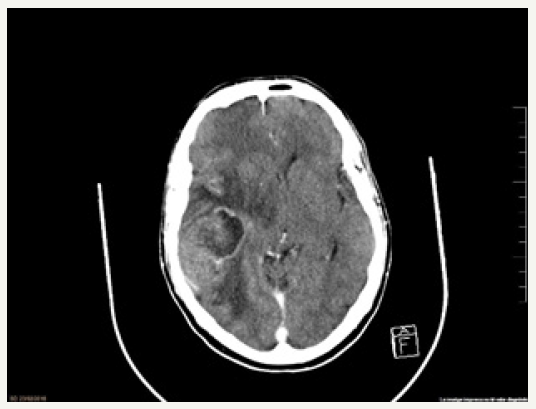

A 57-year-old male presented to the Emergency Department with complaints of stabbing holocraneal headache that didn’t cease with conventional analgesia, vomiting, gait instability and bilateral hearing loss over the last 48 hours. He had previous history of two colon polyps resected in 2012 with anathomopatological results of high and low-grade dysplasia; prostate adenocarcinoma (Gleason 9 T4N1M0) treated in 2015 with transurethral resection, radiotherap and double hormonal treatment; and liver hemangiomas. At presentation, his vital signs were normal. He was aware and oriented with a fluent speech. He had homonymous inferior quadrant-anopsia, central facial palsy and left-sided hemihypoesthesia with no other neurological impairment. He underwent a brain CT scan that showed a nodular lesion (46 x 42 x 42mm) in right temporal lobe with heterogeneous enhancement, extensive vasogenic edema, mass effect and a descending transtentorial herniation (Figure 1), suggestive of a single brain metastasis or a high-grade primary brain neoplasm. Intravenous dexamethasone was started, and he was transferred to an Intermediate Care Unit.

figure 1: Axial brain CT-scan with contrast enhanced lesion in right temporal lobe with extensive vasogenic edema and mass effect.